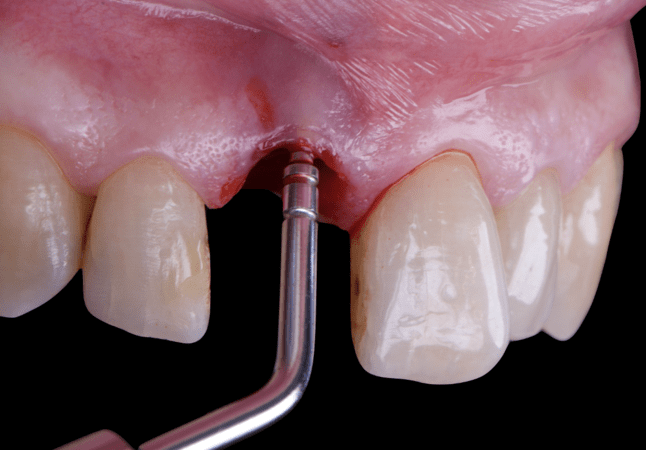

The surgical protocol began with the atraumatic extraction of tooth 1.1 to preserve as much of the alveolar socket as possible. Immediately following extraction, an N1 implant was placed into the socket using a guided surgical approach to ensure ideal three-dimensional positioning. The “one abutment one time” technique was applied to minimize soft tissue manipulation during the healing phase, which is particularly important in esthetic areas.

Given the significant buccal defect, guided bone regeneration (GBR) was performed simultaneously. A mixture of autologous bone and creos™ xenogain™ was applied to the defect and covered with a resorbable creos™ membrane to restore ridge width and support the buccal contour. In addition, a connective tissue graft was harvested and placed in the vestibular region to increase the thickness of keratinized mucosa. This combined approach addressed both hard and soft tissue deficiencies, providing the biological foundation for a stable and esthetic outcome.

On the same day as the surgery, an immediate-load provisional crown was delivered. This restoration was fabricated in acrylic resin and screw-retained on the implant, following the “one abutment one time” principle. The provisional crown was carefully adjusted to avoid occlusal loading while supporting the peri-implant soft tissue architecture during the healing phase.